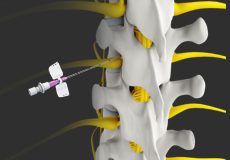

Epidural Spinal Injection

Epidural spinal injection is a non-surgical treatment option utilized for relieving back pain. Spine degenerative conditions such as herniated disc, spinal stenosis and many others may induce back pain due to the compression of the associated spinal nerves. This pain or numbness may extend to the other parts of the body such as hips, buttocks, and legs. Doctors start with non-surgical methods to treat back pain and epidural spinal injection is one of these preferences. In cases where the patient finds no relief from non-surgical methods then finally surgery is recommended.

Epidural Steroid Injections

Epidural steroid injection (ESI) is a minimally invasive approach to treat inflammation of spinal nerves that causes pain in the neck, arms, back and legs. This technique may help relieve back pain in conditions such as spinal stenosis, spondylolysis or herniated discs. In this technique, the steroidal medications are injected into the spinal canal so as to pass down to the inflamed spinal nerve through the epidural space which lies between the covering of the spinal cord and the vertebrae. An ESI contains a corticosteroid medication along with an anesthetic agent which can reduce the inflammation and pain.

Transforaminal Epidural Steroid Injection

The epidural space of the spine is the area between the vertebral bones and the protective dura sac that surrounds the spinal cord and nerves.

Spine Injections

Spine injection is a non-surgical treatment modality recommended for the treatment of chronic back pain. Injection of certain medicinal agents relieves the pain by blocking the nerve signals between specific areas of the body and the brain. The treatment approach involves injections of local anesthetics, steroids, or narcotics into the affected soft tissues, joints, or nerve roots. It may also involve complex nerve blocks and spinal cord stimulation.